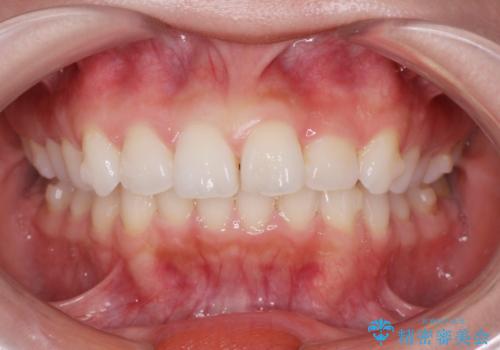

前歯のがたつき気になる。インビザラインモデレート

- 前歯のがたつきが気になるとの事で来院。

噛み合わせを確認したところ上の歯が全体的に前にある状態でした。

患者様は2のプランを選ばれたのでインビザラインモデレートで治療を行いました。

ガタつきがなくなり満足して頂けました。